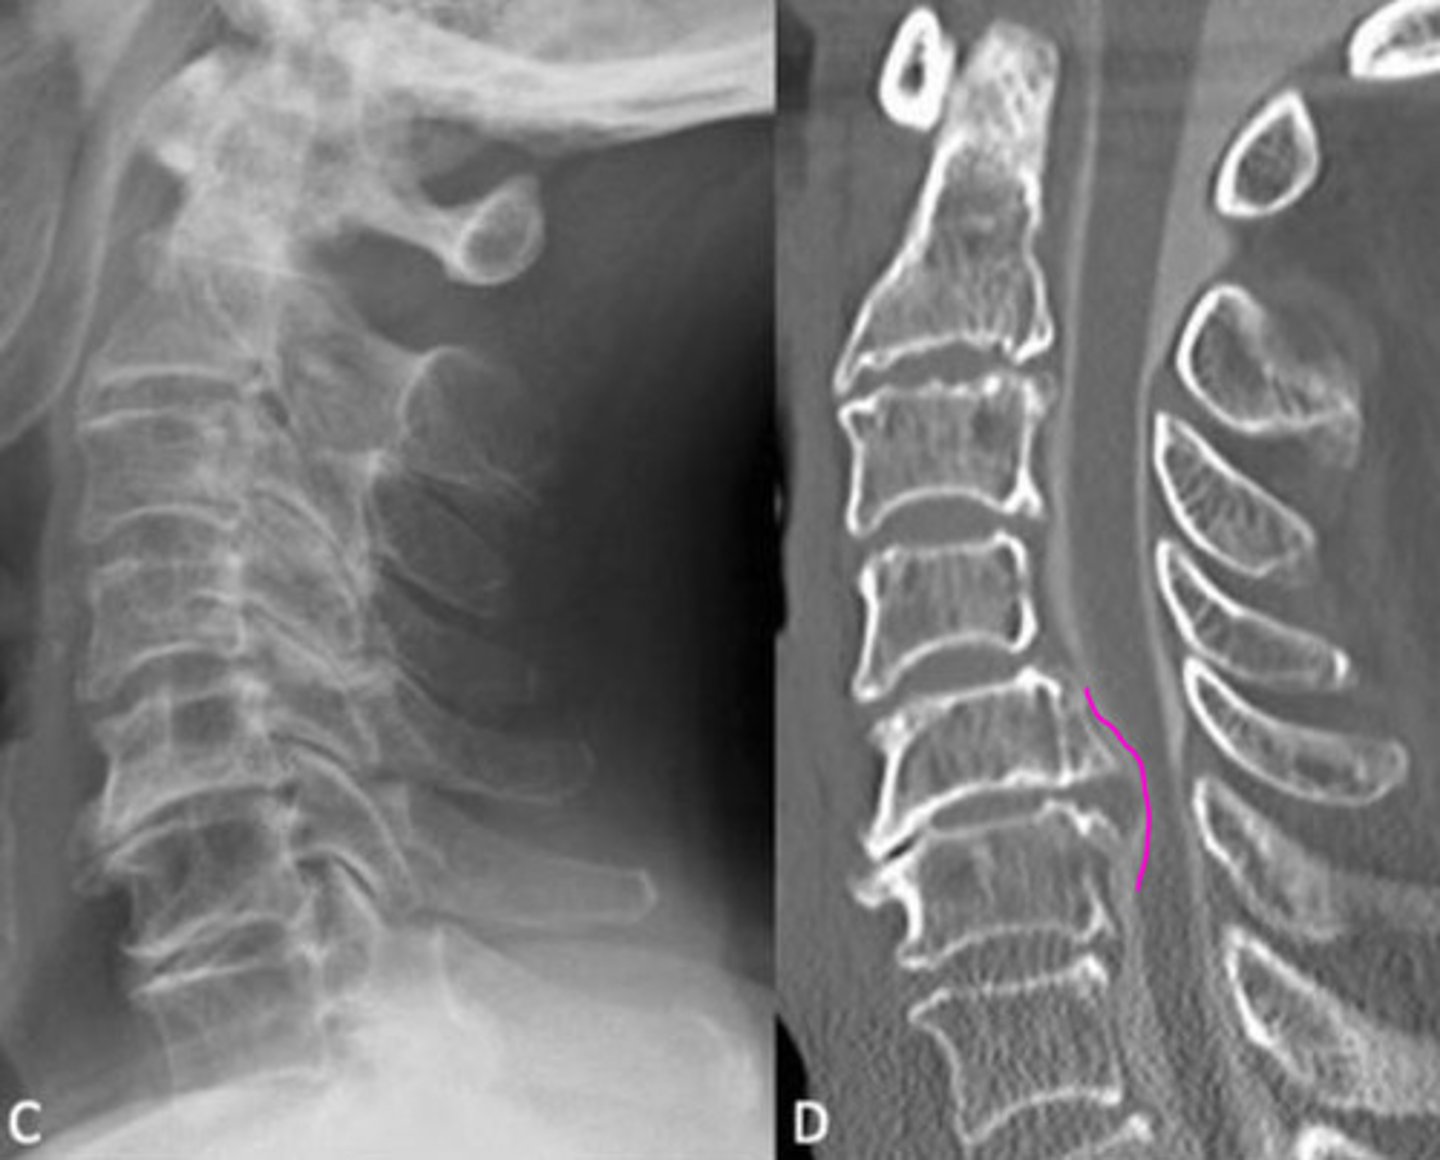

CT

What has the best image of cortical bone?

DISH (mid body to mid body)

What is the arrow pointing at?

Mid body

Where does the ALL attach to the vertebrae?

DISH (mid body flow of the anterior vertebral line)

What is wrong with this image?